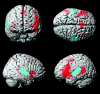

Results: Control and autistic subjects showed similar language-activation networks, with 2 notable differences. Control subjects showed significantly increased activation in the left posterior insula compared with autistic subjects (P < .05, false discovery rate), and autistic subjects showed increased bilaterality of receptive language compared with control subjects. Higher receptive-language scores on standardized testing were associated with greater activation of the posterior aspect of the left Wernicke area. A higher verbal IQ was associated with greater activation of the bilateral Broca area and involvement of the prefrontal cortex and lateral premotor cortex.

Conclusions: Control subjects showed greater activation of the posterior insula during receptive language, which may correlate with impaired emotive processing of language in autism. Subjects with autism showed greater bilateral activation of receptive-language areas, which was out of proportion to the differences in hand preference in autism and control populations.